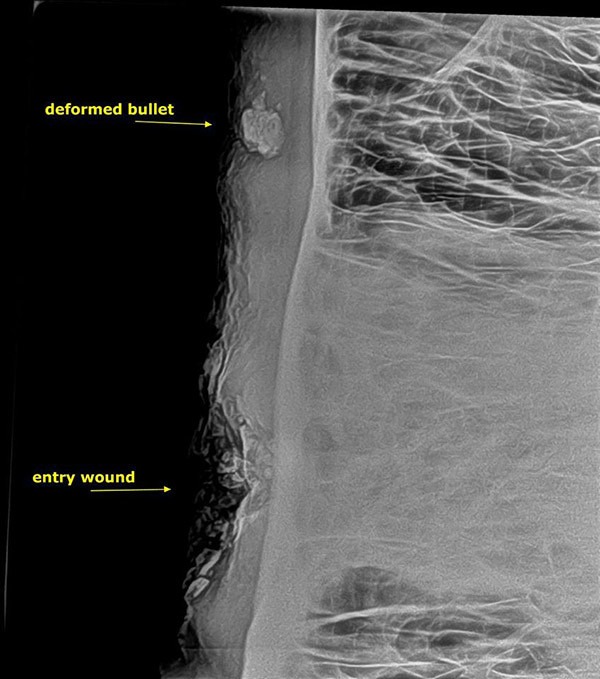

Further examination and X-rays revealed that Pretty Boy had been shot several weeks earlier. A deformed bullet was lodged inside his skull, having narrowly missed killing him.

According to AWARE Trust Zimbabwe, the shot was fired slightly too high for a fatal hit. Instead, the bullet glanced off his skull, causing a depression fracture in the sinus bones before embedding itself nearly two inches from the entry wound.

Working carefully, the vets removed fragments of shattered bone, thoroughly cleaned and disinfected the wound, and administered strong antibiotics to fight the infection. The X-ray confirmed just how close Pretty Boy had come to death — the bullet was less than an inch away from a lethal impact.